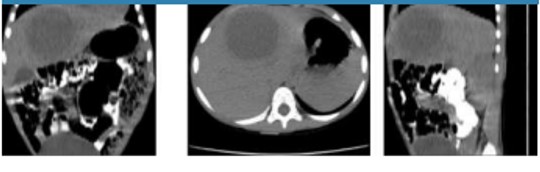

The management based on antibiotic therapy continued on intravenous metronidazole at 1.5 g per day for 10 days. During the evolution of the case the patient underwent a pre contrast CT in order to qualify whether the space-occupying lesion varied from iso to hyperdense, but with the peripheral contrast enhancement because this is a contrast CT feature when the lesion corresponds with a liver abscess. For such imaging examination, a normal protocol of creatinine and urea is verified. In addition, the status of the alpha-fetoprotein tumor marker is evaluated, resulting negative. Figure 3 shows the contrast CT of the space-occupying lesion.

The double-target distinctive feature of the amebic liver abscess on contrast-enhanced CT consisted of three segments, 1) a hypodense cavity, 2) an inner hyperdense ring that surrounds the central hypodense cavity, and 3) an external hypodense zone. This distinctive feature cannot be verified on CT scan as it is shown in Figure 3; therefore the lesion cannot be differentiated from the benign solid and malignant masses.

Nevertheless, this follow-up contrast-enhanced CT scan three weeks after starting antibiotic therapy shows an apparent reduction in the size of the hepatic space-occupying lesion. In this sense, the use of digital image processing techniques is considered as a computer-aided tool to support the diagnosis18. Thus, the space-occupying lesion was segmented from the two three-dimensional CT images without and with contrast, which are shown in Figure 2 and Figure 3, respectively. The volume of the two the three-dimensional pathological structures is quantified, and then their values were compared in order to determine if the size of the liver lesion varied.

The results of the liver lesion segmentation from the CT scan before and after antibiotic therapy shown that the size of this lesion decreased between two explorations; the volumes quantified were of 63.2 cm3 and of 58.9 cm3, respectively. Further, the result associated with contrast-enhanced CT segmentation documented slight decrease in size of the lesion 21 days after first volume assessment from an ultrasonography examination of 65.5 cm3.